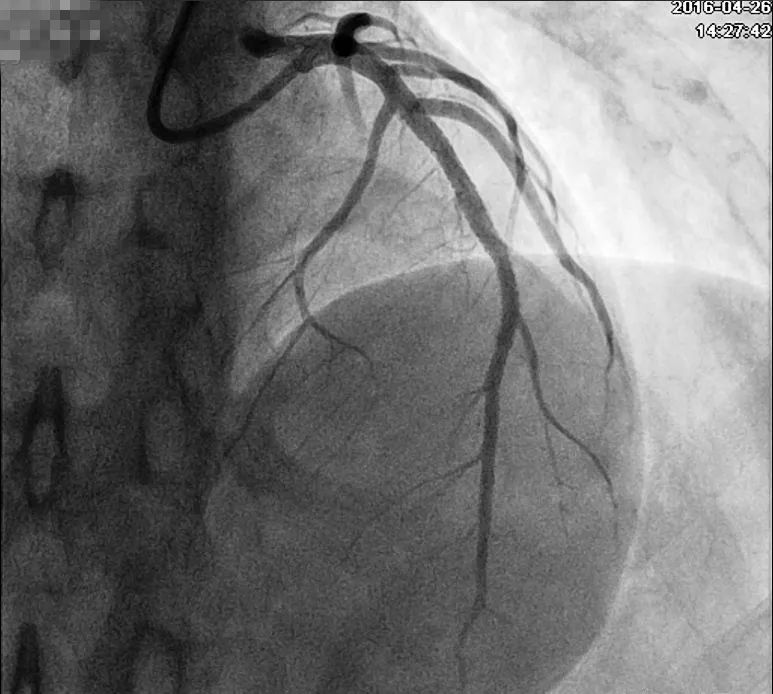

回顾患者病例特点:青年男性,有典型心绞痛发作病史,心电图有特征性改变及演变(胸痛发作时心电图正常;胸痛缓解时,V2~V5导联T波倒置),考虑Wellens综合征。行冠状动脉造影检查示左前降支(LAD)近中段80%~90%弥漫性狭窄,血流慢(图6),右冠近段狭窄20%~30%,回旋支开口狭窄20%~30%(图7)。于LAD置入2枚支架,复查造影提示支架置入处无残余狭窄(图8)。术后规律服用上述药物治疗,未再发作心绞痛。

图8